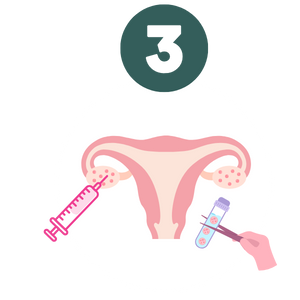

O processo de análise começa com a observação detalhada das imagens geradas pelo ultrassom morfológico. Isso inclui verificar a normalidade do útero, a integridade da placenta, membranas uterinas, o desenvolvimento fetal, a adequada frequência cardíaca fetal e o fluxo sanguíneo útero-placentário-fetal. O ultrassonografista avalia a anatomia do bebê, certificando-se de que os ossos, órgãos e outros sistemas, como o coração, cérebro, estômago e rins estejam se desenvolvendo conforme esperado. É igualmente importante observar a presença de batimentos cardíacos regulares e os movimentos respiratórios fetais no terceiro trimestre da gestação.

- Útero: Visualização da estrutura e posicionamento.

- Fluxo sanguíneo: Inspeção dos vasos sanguíneos e da circulação.